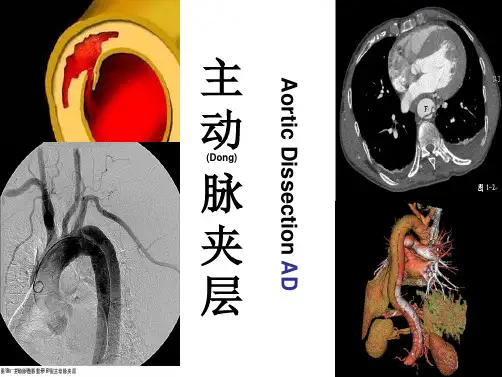

1、 90%病人首发症状为突发的、持续 性、进行性加重的剧烈胸痛(Tong),呈刺痛、 撕裂样或刀割样疼痛,病人往往不能忍受, 此时大汗淋漓,含服硝酸甘油无效。多数

患者同时伴有难以控制的高血压;

疼痛部位提示分离起始部位: 前胸部:近端夹层;肩胛间(Jian)区:起

最大危害是死亡。不进行恰当和及 时的治疗,破裂(Lie)的机会非常大,死亡率 也非常高。以往的文献报告,1周内的死 亡率高达50%,一个月内的死亡率在6070%之间。